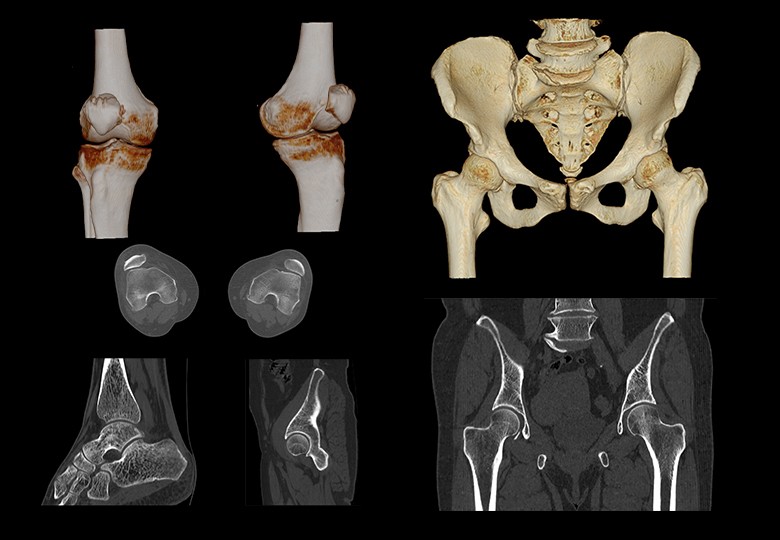

Bone Scan